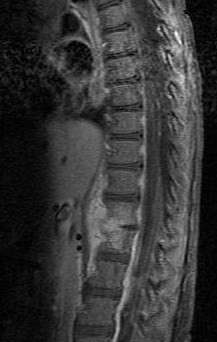

Diagnosis is usually apparent on MRI although plain X-rays and CT examinations can be suggestive. The MRI will reveal air changes in the disc and possibly even external involvement involving the bone or epidural regions. A biopsy may be performed and helps with diagnosis in some cases but often an organism is not obtained. C-reactive protein levels and ESR levels will be elevated and are useful for treatment. Often, the white blood cell count will be normal and the patient will be afebrile.